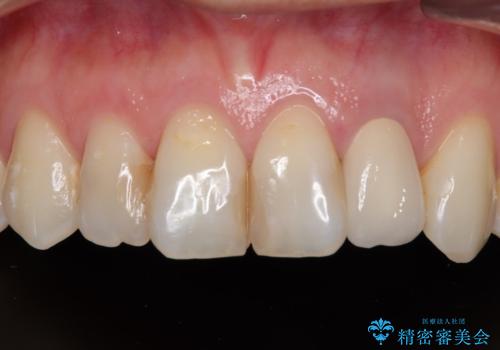

保険診療の黄ばんできた前歯をオールセラミッククラウンで自然な歯に